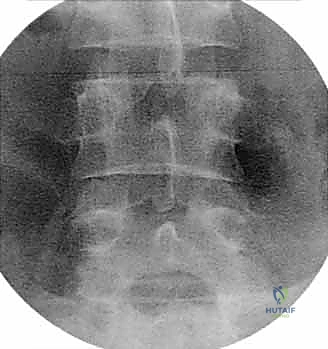

- الأشعة السينية الديناميكية (Dynamic X-rays): صور في وضعيات الانحناء للأمام والخلف لتقييم مدى عدم استقرار العمود الفقري (الانزلاق الفقري - Spondylolisthesis).

- التصوير المقطعي المحوسب (CT Scan): يقدم تفاصيل دقيقة للغاية عن البنية العظمية، وهو ضروري جداً للتخطيط الجراحي، خاصة في حالات استئصال الجسم الفقري أو وجود تعظم شديد.